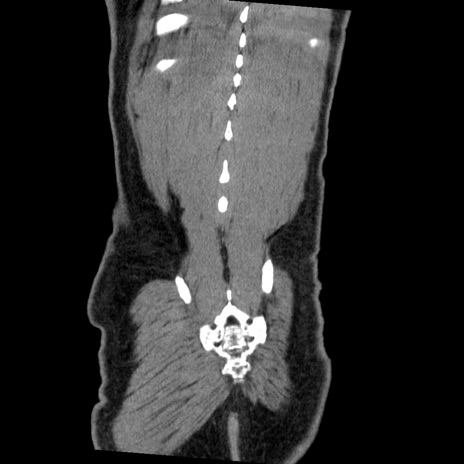

症例22(冠状断像)

【症例】50歳代男性

【主訴】腹痛

【現病歴】AVMからの被殻出血のため回復期リハ病棟入院中。 本日午後3時頃急に下腹部痛が出現した。

【既往歴】AVM、被殻出血、虫垂炎、高血圧

【身体所見】意識晴明、左半身不全麻痺、会話の理解は良好、36.5°C、腹部:膨隆、全体に板状硬、下腹部正中に圧痛点あり、反跳痛-、筋性防御不明、右下腹部にope scar

【データ】WBC 9400、CRP 0.06